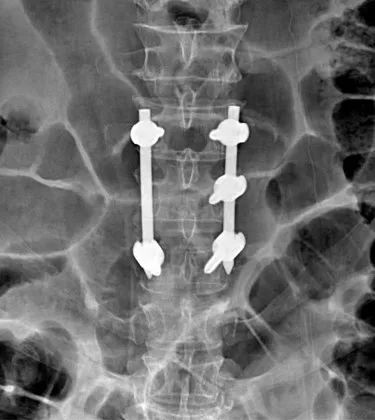

经术前充分准备,手术过程顺利,在系统的引导下精准置钉,出血仅 50 ml。术中置钉复位内固定完毕后经 O 臂三维重建扫描见腰 1 椎体高度复位满意,螺钉位置良好,手术成功。

在这台手术中,智能导航系统成了医生的「得力助手」。此次 O 臂导航下经皮螺钉植入,骨科手术团队 10 分钟内便完成了 5 根螺钉的植入。由此避免了常规术中穿刺过程需反复透视观察。